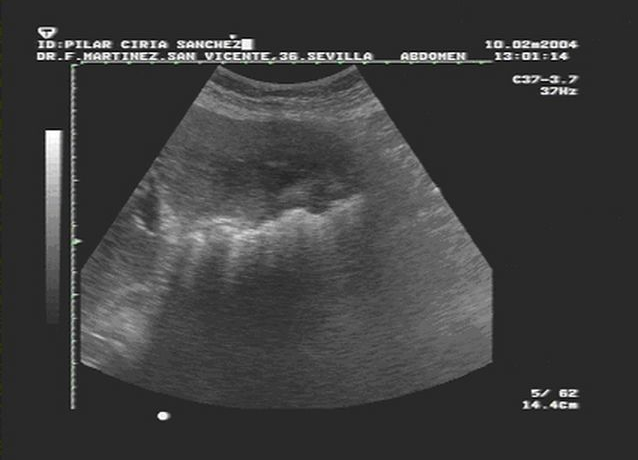

Nódulo mamario palpable abordaje diagnóstico

Dentro de las diversas patologías de la glándula mamaria, el nódulo ocupa un lugar preponderante en la variedad de manifestaciones, tanto de enfermedad benigna como maligna. Actualmente, es uno de los principales motivos de consulta médica. Es imprescindible disponer de un adecuado abordaje diagnóstico para